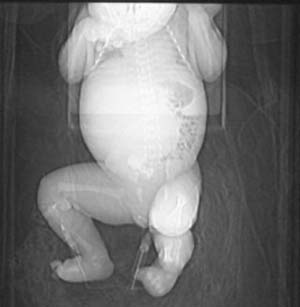

这个女孩刚出生一天,肚子比较大,没任何症状.比较少见,请大家积极发言!!

这个病例定位诊断:1、可以肯定肿块不在肝脏。2、肿块在腹膜后,因为肠管向前侧方推移,肾脏明显向后推挤,腹主动脉及下腔静脉被肿块包绕。

定性诊断比较困难,该病例肿块为实质性,小儿最常见的腹膜后肿瘤第一位应该是-----神经母细胞瘤!

我的意见是-----定位诊断是“1、可以肯定肿块不在肝脏。2、肿块在腹膜后,因为肠管向前侧方推移,肾脏明显向后推挤,腹主动脉及下腔静脉被肿块包绕。”

右中下腹部囊实性密度影,内有小细条状钙化影,胃及腹部肠管受压向左移位,肾脏受压向后移位,腹主动脉及下腔静脉包饶。考虑腹膜后畸胎瘤可能性大。